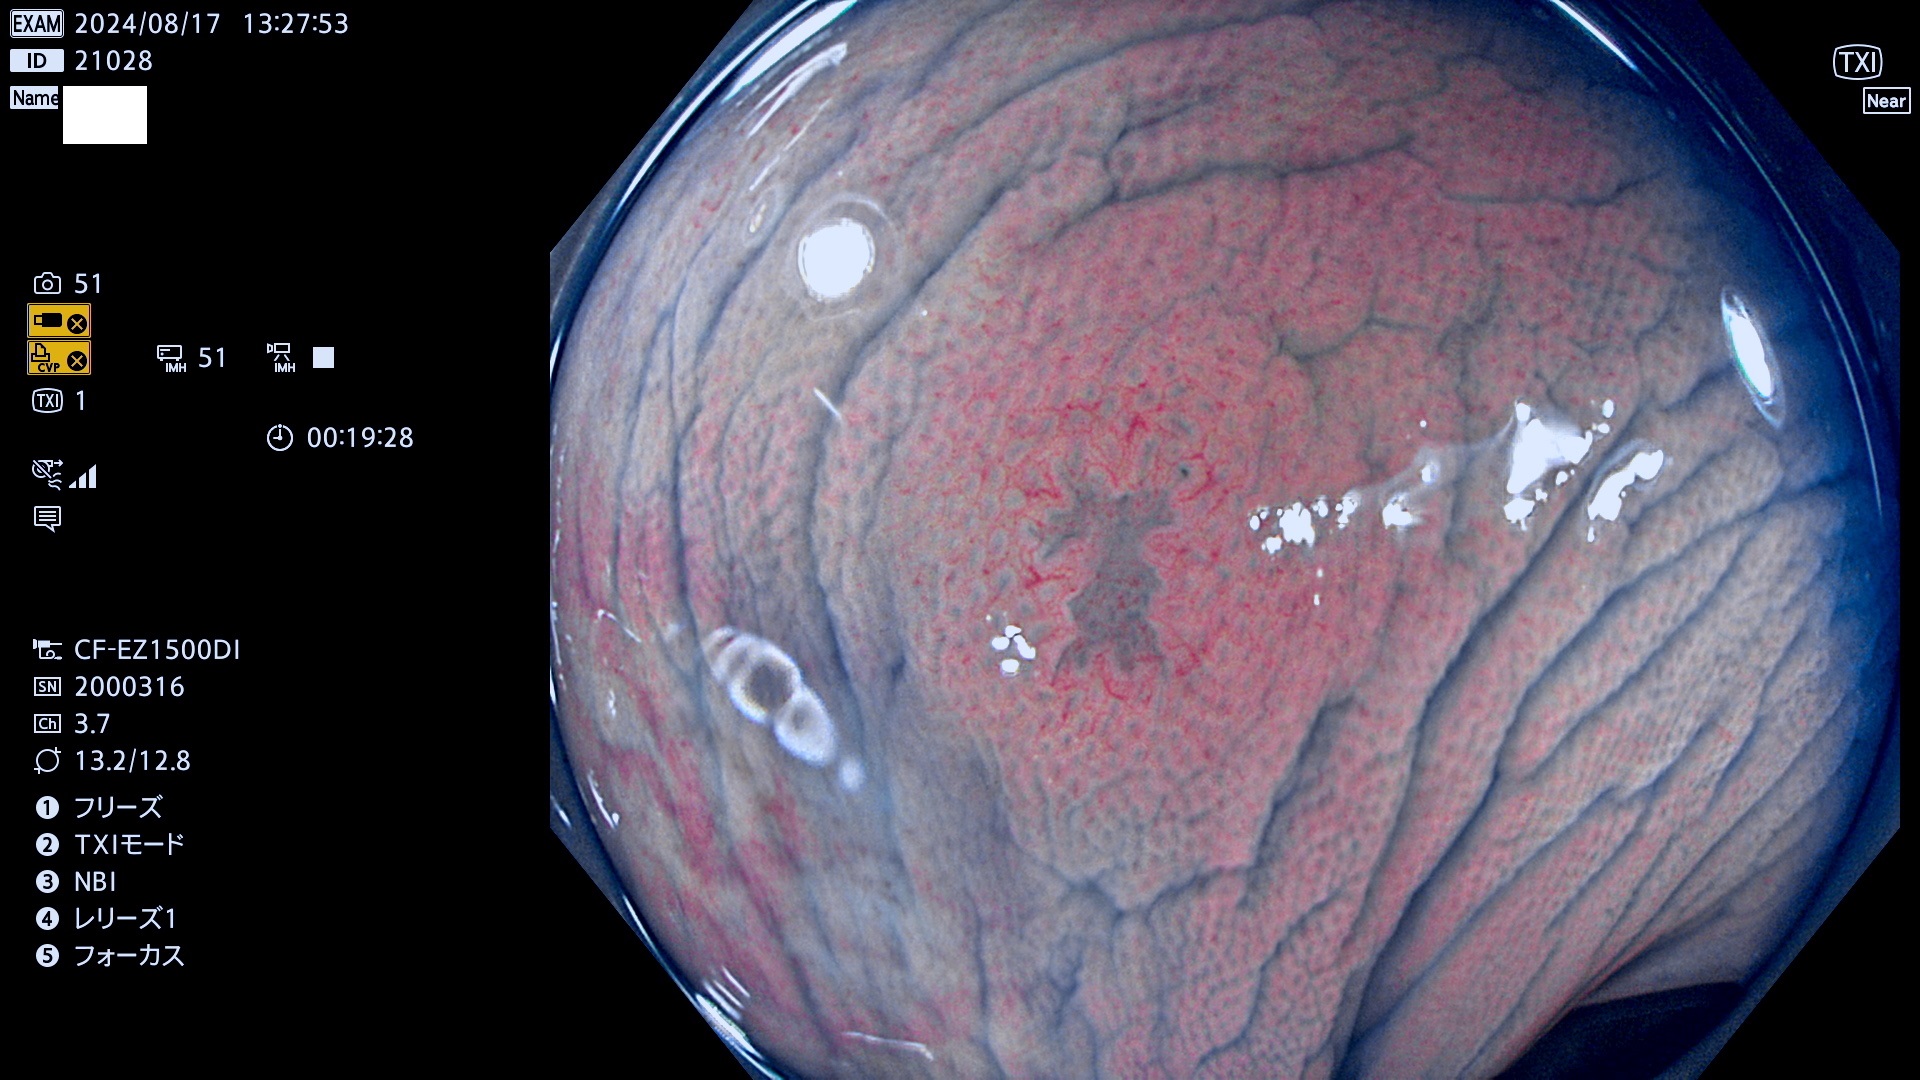

今週のUb、Uc型腺腫

完全に平坦な物をUb、陥凹している物をUcと呼びます。最も発見が難しく危険な病変です。

抽出の対象期間 2024年8月15日〜8月18の4日間(33件の検査)7件 (7/33=21%)